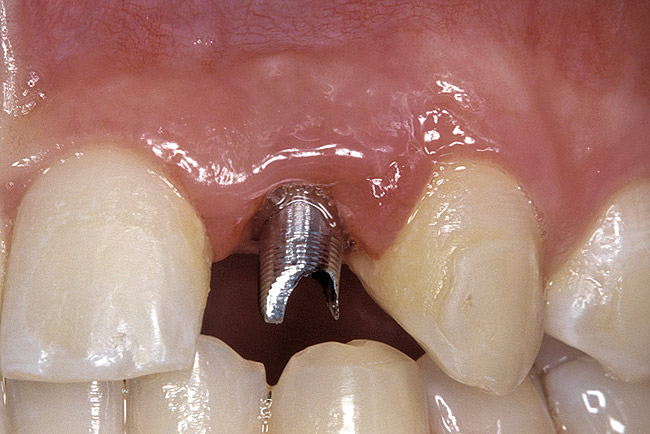

Figure 2  DIAGNOSTIC INFORMATION Root convergence, buccal view.

Figure 2